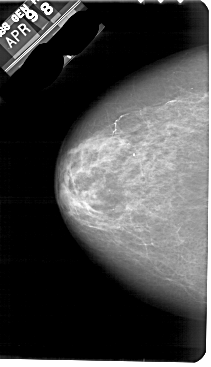

A_1700_1.RIGHT_CC

RIGHT_CC LINES 5491 PIXELS_PER_LINE 3331 BITS_PER_PIXEL 12 RESOLUTION 43.5 OVERLAY